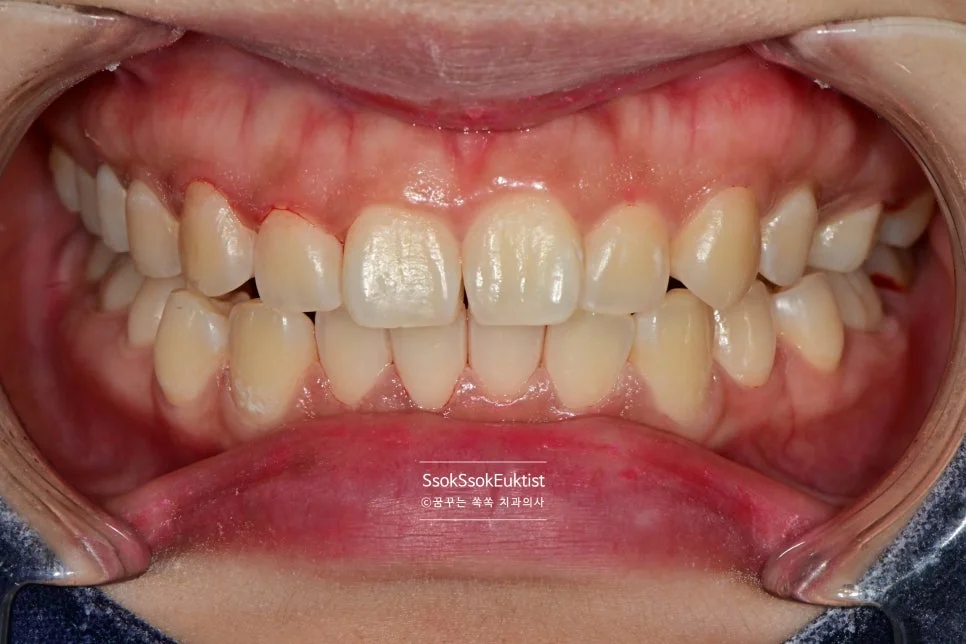

스케일링 전 치석 착색 상태

Before — 스케일링 전

수면 스케일링 후 깨끗한 치아

After — 수면 스케일링 후

왼쪽 위 치경부 우식을 레진으로 예쁘게 치료한 후 스케일링도 시행하였는데요. 비교적 깨끗하고 건강해진 모습이 보입니다~^^